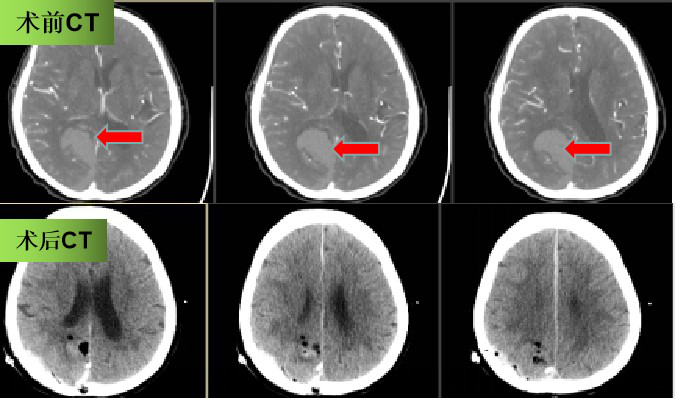

动脉瘤是颅内的定时炸弹,一旦破裂,患者有生命危险,而4名患者中另一位67岁的患者同样源于此病因,就诊前5小时出现了意识障碍伴右侧肢体无力,在救护车转运期间及出现了意识下降至深昏迷,呼之不应,脑血管CT成像提示“脑出血,脑血管畸形,可疑左侧大脑前动脉动脉瘤”。患者手术风险极大,但已经出现脑疝,生命危在旦夕,刻不容缓,遂紧急行开颅手术。郭毅医师在显微镜下清除脑内血肿,探查发现患者左侧大脑前动脉瘤破裂,考虑为本次脑出血的致病根源,予手术夹闭,探查发现右侧后交通动脉瘤,同时行手术夹闭,消灭了以后患者此处动脉瘤破裂出血的危险。“这种类型的患者病情极其凶险,出血量大,治疗极其困难,若不及时手术治疗,很难存活。”郭毅说。

患者手术前后头颅CT,血肿清除满意